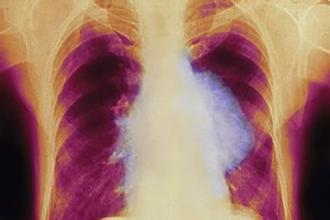

胸水往往是肺癌恶化到一定程度后出现的并发症,治疗上需要针对原发病灶的同时,还要对胸水进行对症治疗,才能做到标本兼治。

我的一位患者71岁老人,18年5月无明显诱因出现右侧胸痛,持续4天后入院检查发现肺癌伴胸水,行化疗并抽胸水治疗,症状得到缓解,但随后胸水复发,且化疗副作用明显,综合考虑后转中医治疗。